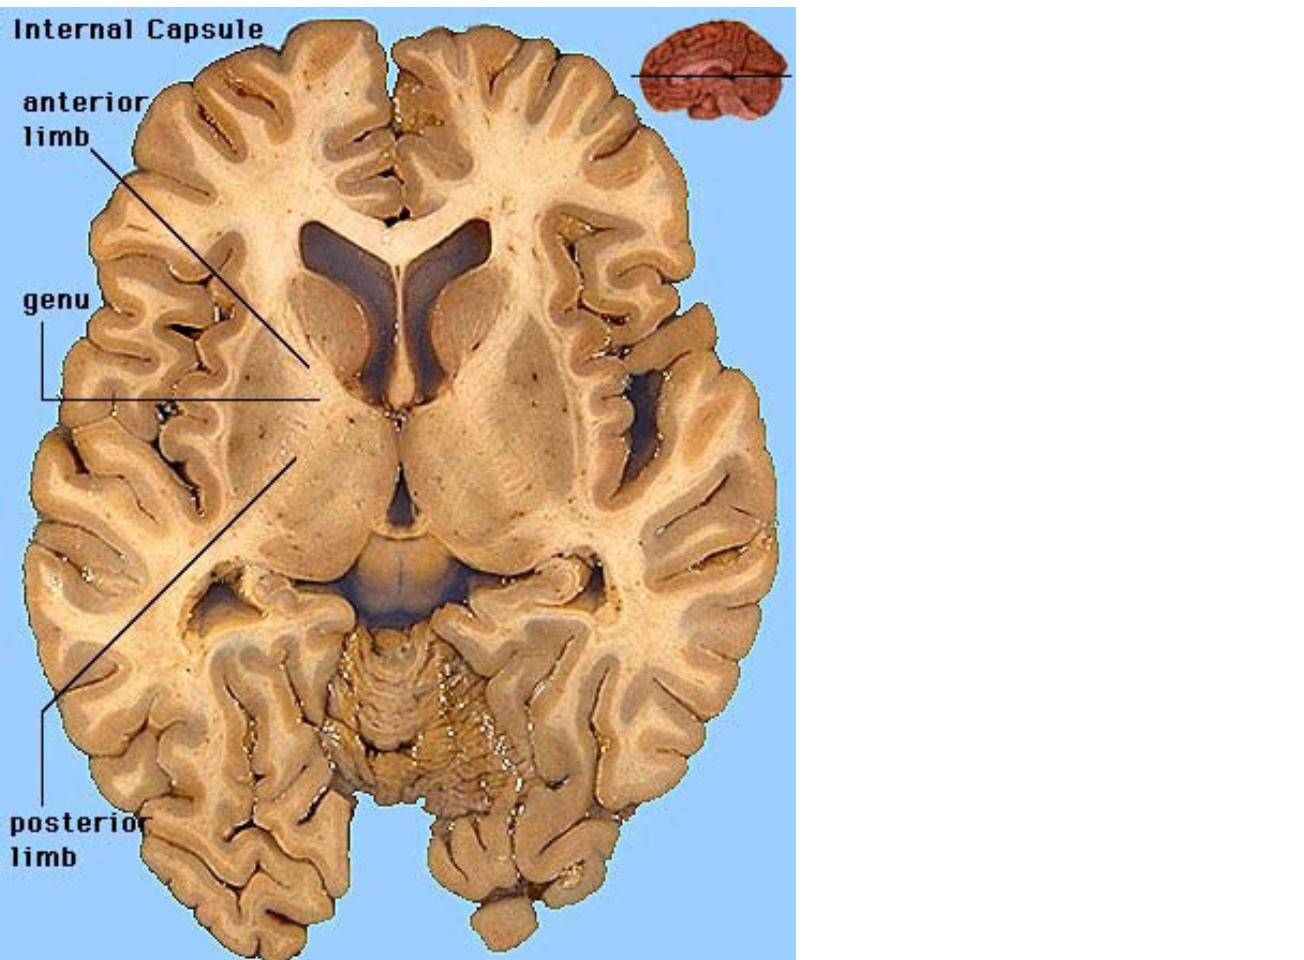

Corticospinal tract

A

Originates in multiple

cortical areas

– Primary motor cortex

– Pre-motor cortex

* Route via:

– Internal capsule

* Between Thalamus &

Basal Ganglia

– Cerebral peduncles

* Contralateral crossing at

the pyramids (medulla)

internal capsule (horizontal view)